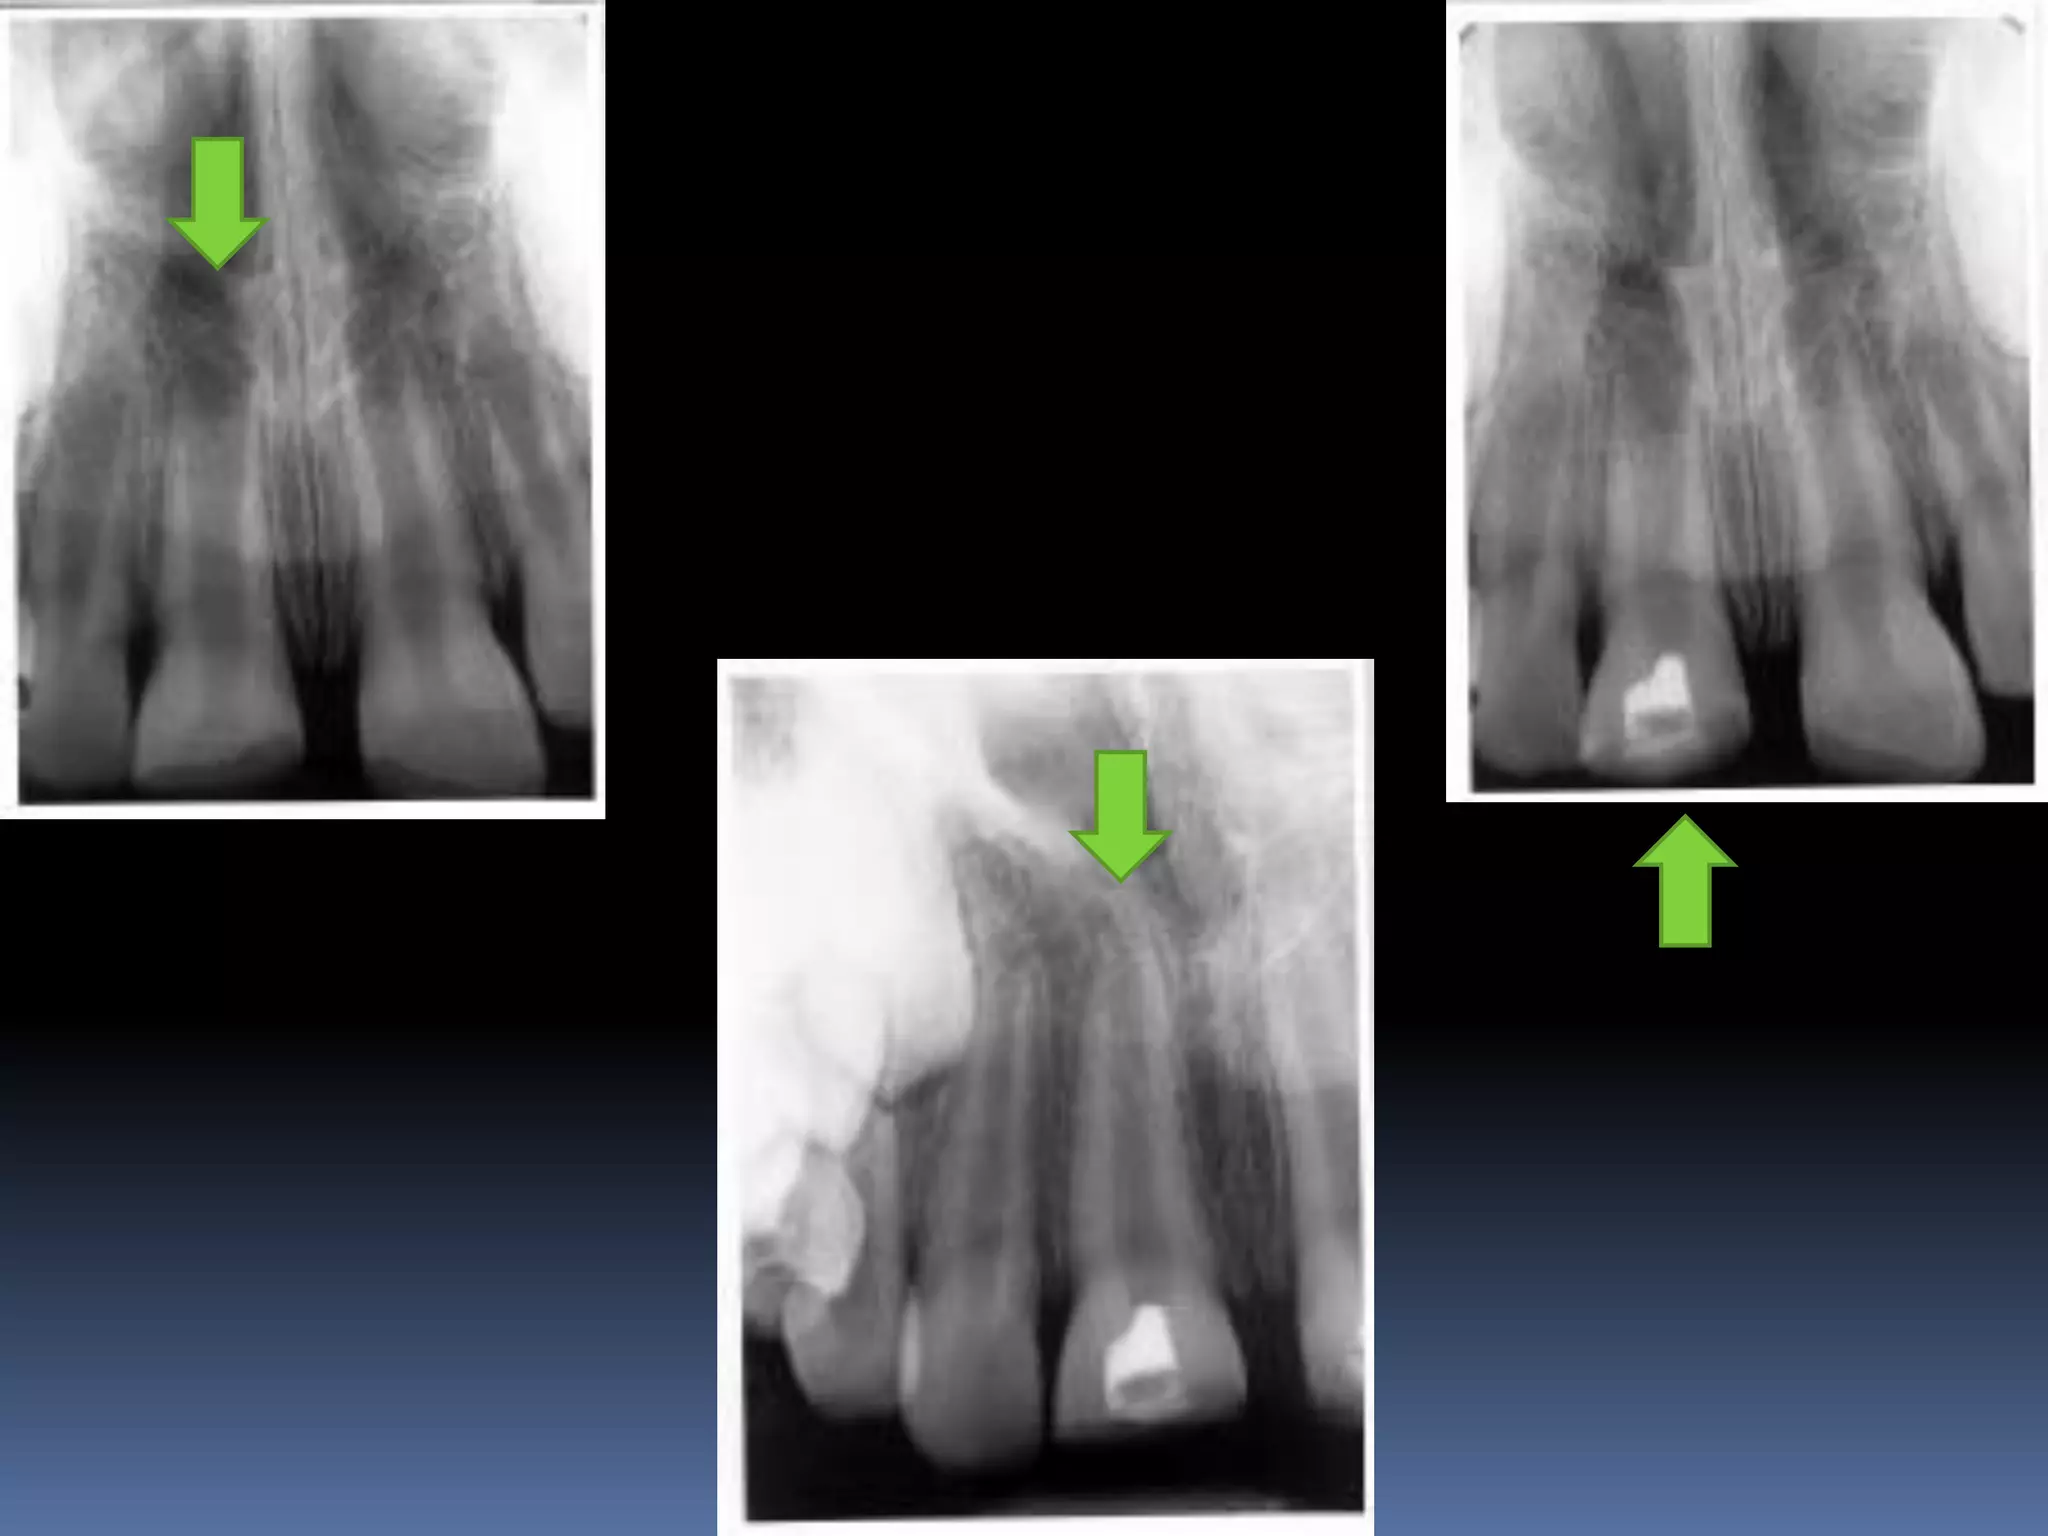

OPEN APEX  Anopen apex is the developing root of an immature tooth until apical closure occurs .  Apical closure occurs 2-3 yrs after tooth eruption  Any injury to the pulp at this stage will stop the closure of the apex  Such a tooth will have short , thin walls at the apical portion of the root

• 32.

 Open apexcan also be caused by extensive resorption of a previously mature apex after orthodontic treatment or severe periapical inflammation

Diagnosis and assessment: History  Subjective symptoms  Diagnostic tests  Radio graphs A radiolucent area usually surrounds the apex of an immature root with a healthy pulp

• 34.

OPEN APEX VITAL PULP APEXOGENESIS NONVITAL PULP APEXIFICATION

APEXOGENESIS A Vital Pulp Therapyprocedure performed to encourage continued physiologic development and formation of the root end. Since the main objective is to maintain the vitality of the radicular pulp the pulp must be vital and capable of repair

• 41.

APEXIFICATION Induction of acalcific barrier or creation of an artificial barrier across an open apex Technique: Local anesthesia and Rubber Dam isolation Access cavity preparation and extirpation of the pulp Working length is established slightly short of the apex [to prevent injury to apical tissues] Instrumentation and copius irrigation Drying the canal and introducing MTA into the canal

• 42.

 Packing MTAusing endodontic pluggers or special system like MAP SYSTEM [Micro Apical placement]  MTA acts as an artificial barrier against which Gutta percha can be condensed.  Calcium hydroxide produces a biologic barrier but takes longer time.